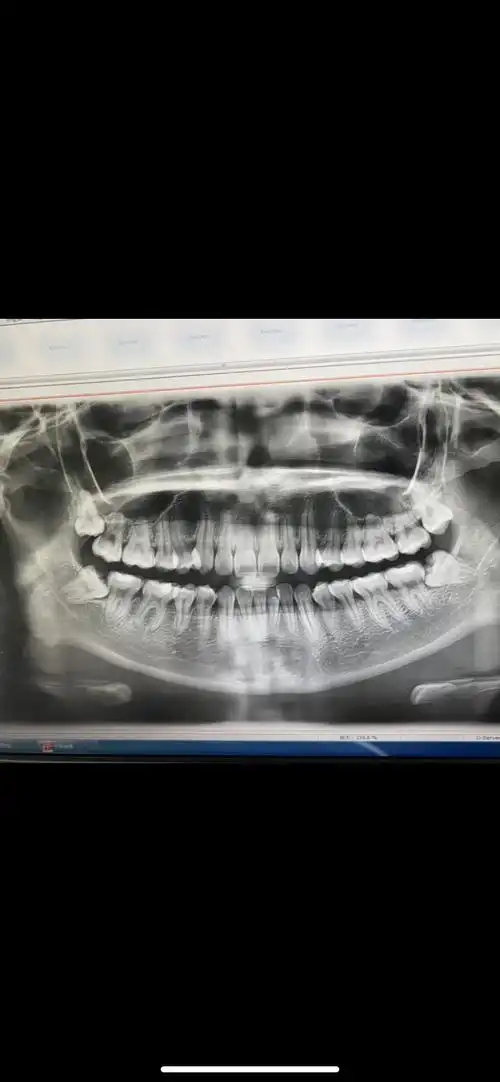

拍摄"全景片",有时还会拍摄口腔cbct,预估智齿的位置,牙根数目及形态